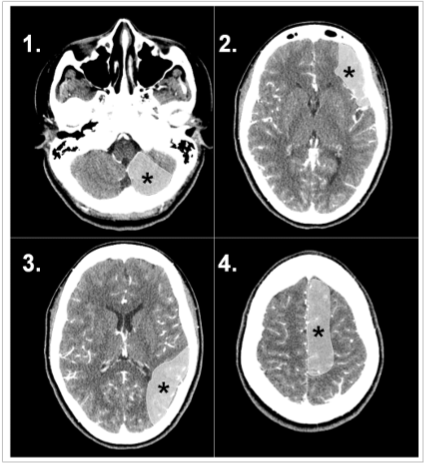

A doença vascular encefálica isquêmica pode determinar diferentes síndromes clínicas a depender do território arterial acometido. A percepção destas síndromes clínicas informadas no pedido médico pode auxiliar o radiologista na percepção de sinais precoces de isquemia intracraniana.

Com base na análise das imagens apresentadas, o território arterial acometido e as respectivas síndromes clínicas proporcionadas são, respectivamente: